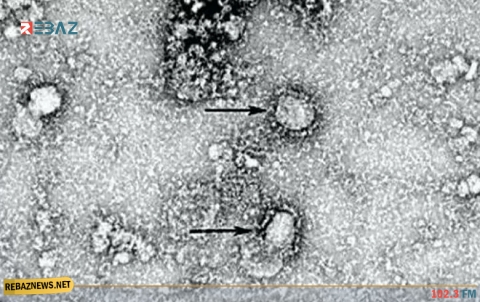

أعراض فيروس كورونا